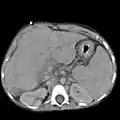

Other scans performed in particular circumstances include CT of the abdomen, and magnetic resonance cholangiopancreatography – MRI of the pancreatic and bile ducts.

Liver cirrhosis as seen on a CT of the abdomen in transverse orientation